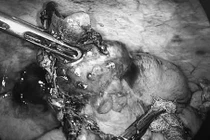

Trước tình trạng nguy kịch, các bác sĩ đã chỉ định phẫu thuật cấp cứu. Ban đầu, người bệnh được nội soi ổ bụng thăm dò, tuy nhiên ghi nhận nhiều dịch bẩn, tổ chức nhầy lan tỏa khắp ổ bụng, phúc mạc viêm đỏ, vùng hố chậu phải có khối cứng chắc, thâm nhiễm, không di động. Ê-kíp phẫu thuật quyết định chuyển mổ mở để xử trí triệt để.

Trong quá trình phẫu thuật, các bác sĩ xác định nguyên nhân là viêm phúc mạc do vỡ khối u nhầy lớn xuất phát từ ruột thừa. Khối u kích thước khoảng 15 cm, đã vỡ, tổ chức nhầy lan rộng và xâm lấn thành bụng vùng hố chậu phải, không còn nhận diện rõ hình thể ruột thừa.

Ê-kíp phẫu thuật do Bác sĩ Nguyễn Văn Dũng – Trưởng khoa Ung bướu 1, Bệnh viện Bãi Cháy trực tiếp thực hiện - Ảnh BVCC

Ê-kíp phẫu thuật do Bác sĩ Nguyễn Văn Dũng, Trưởng khoa Ung bướu 1, Bệnh viện Bãi Cháy trực tiếp thực hiện đã tiến hành cắt đại tràng phải, vét hạch, làm hậu môn nhân tạo hồi tràng, rửa sạch ổ bụng và đặt dẫn lưu.